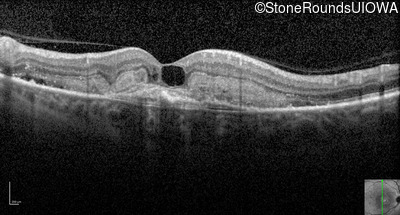

Optical Coherence Tomography - Right - 20/250

Exemplar / OCT Stack